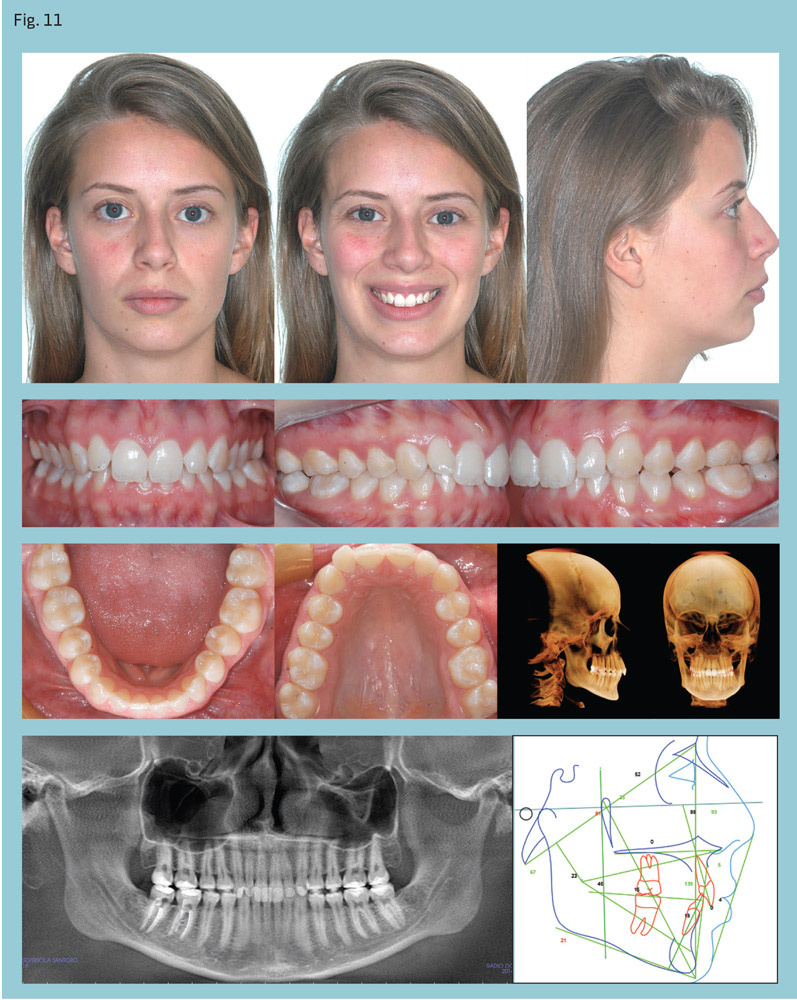

A 20-year-old woman presented with a Class II, Division 2, subdivision malocclusion with mild maxillary crowding (Fig. 11). Her overbite was almost 100 percent and lower midline was deviated to the left. Her condition was compounded by a left posterior crossbite. Cephalometric analysis revealed a dolichofacial pattern and mandibular retrognathia.

After four months of leveling and alignment, PowerScope was placed (Figs. 12-13). The Class II was corrected in three months (Fig. 14) and PowerScope removed. After another three months for coordinating the arches and detailing the occlusion, fixed appliances were debonded, completing 10 months of active treatment (Fig. 15).